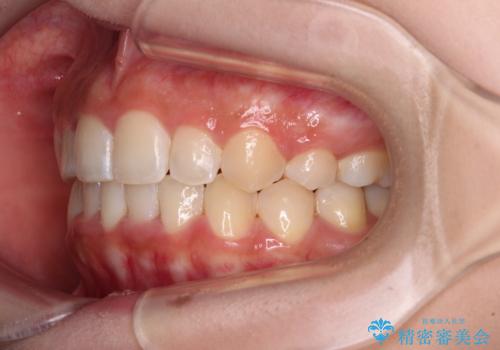

- クリアブラケット

- 上顎の八重歯と、上下前歯のデコボコを気にして来院された患者様です。

奥歯の咬み合わせを見ると、上顎臼歯が下顎に対して前方にあり、叢生改善により口元が突出する顔貌ではなかったため、上顎左右第一小臼歯2本を抜歯し、ワイヤー装置にて矯正治療を行うこととしました。

前歯部のデコボコがなくなったため、歯磨きしやすくなり、非常に清潔な状態になりました。